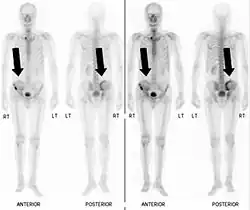

Bone scintigraphy

Also known as a bone scan, bone scintigraphy involves the injection of a small amount of radioactive tracer into the bloodstream. This tracer decays and emits radioactive energy which can be detected by a special camera. The camera produces a black and white image where areas shown as dark black indicate bone damage of some kind. If there is a black spot in the lumbar vertebrae (e.g. L5) this indicates damage and potentially spondylolysis. If this test is positive, a CT scan is usually ordered to confirm spondylolysis.[16]